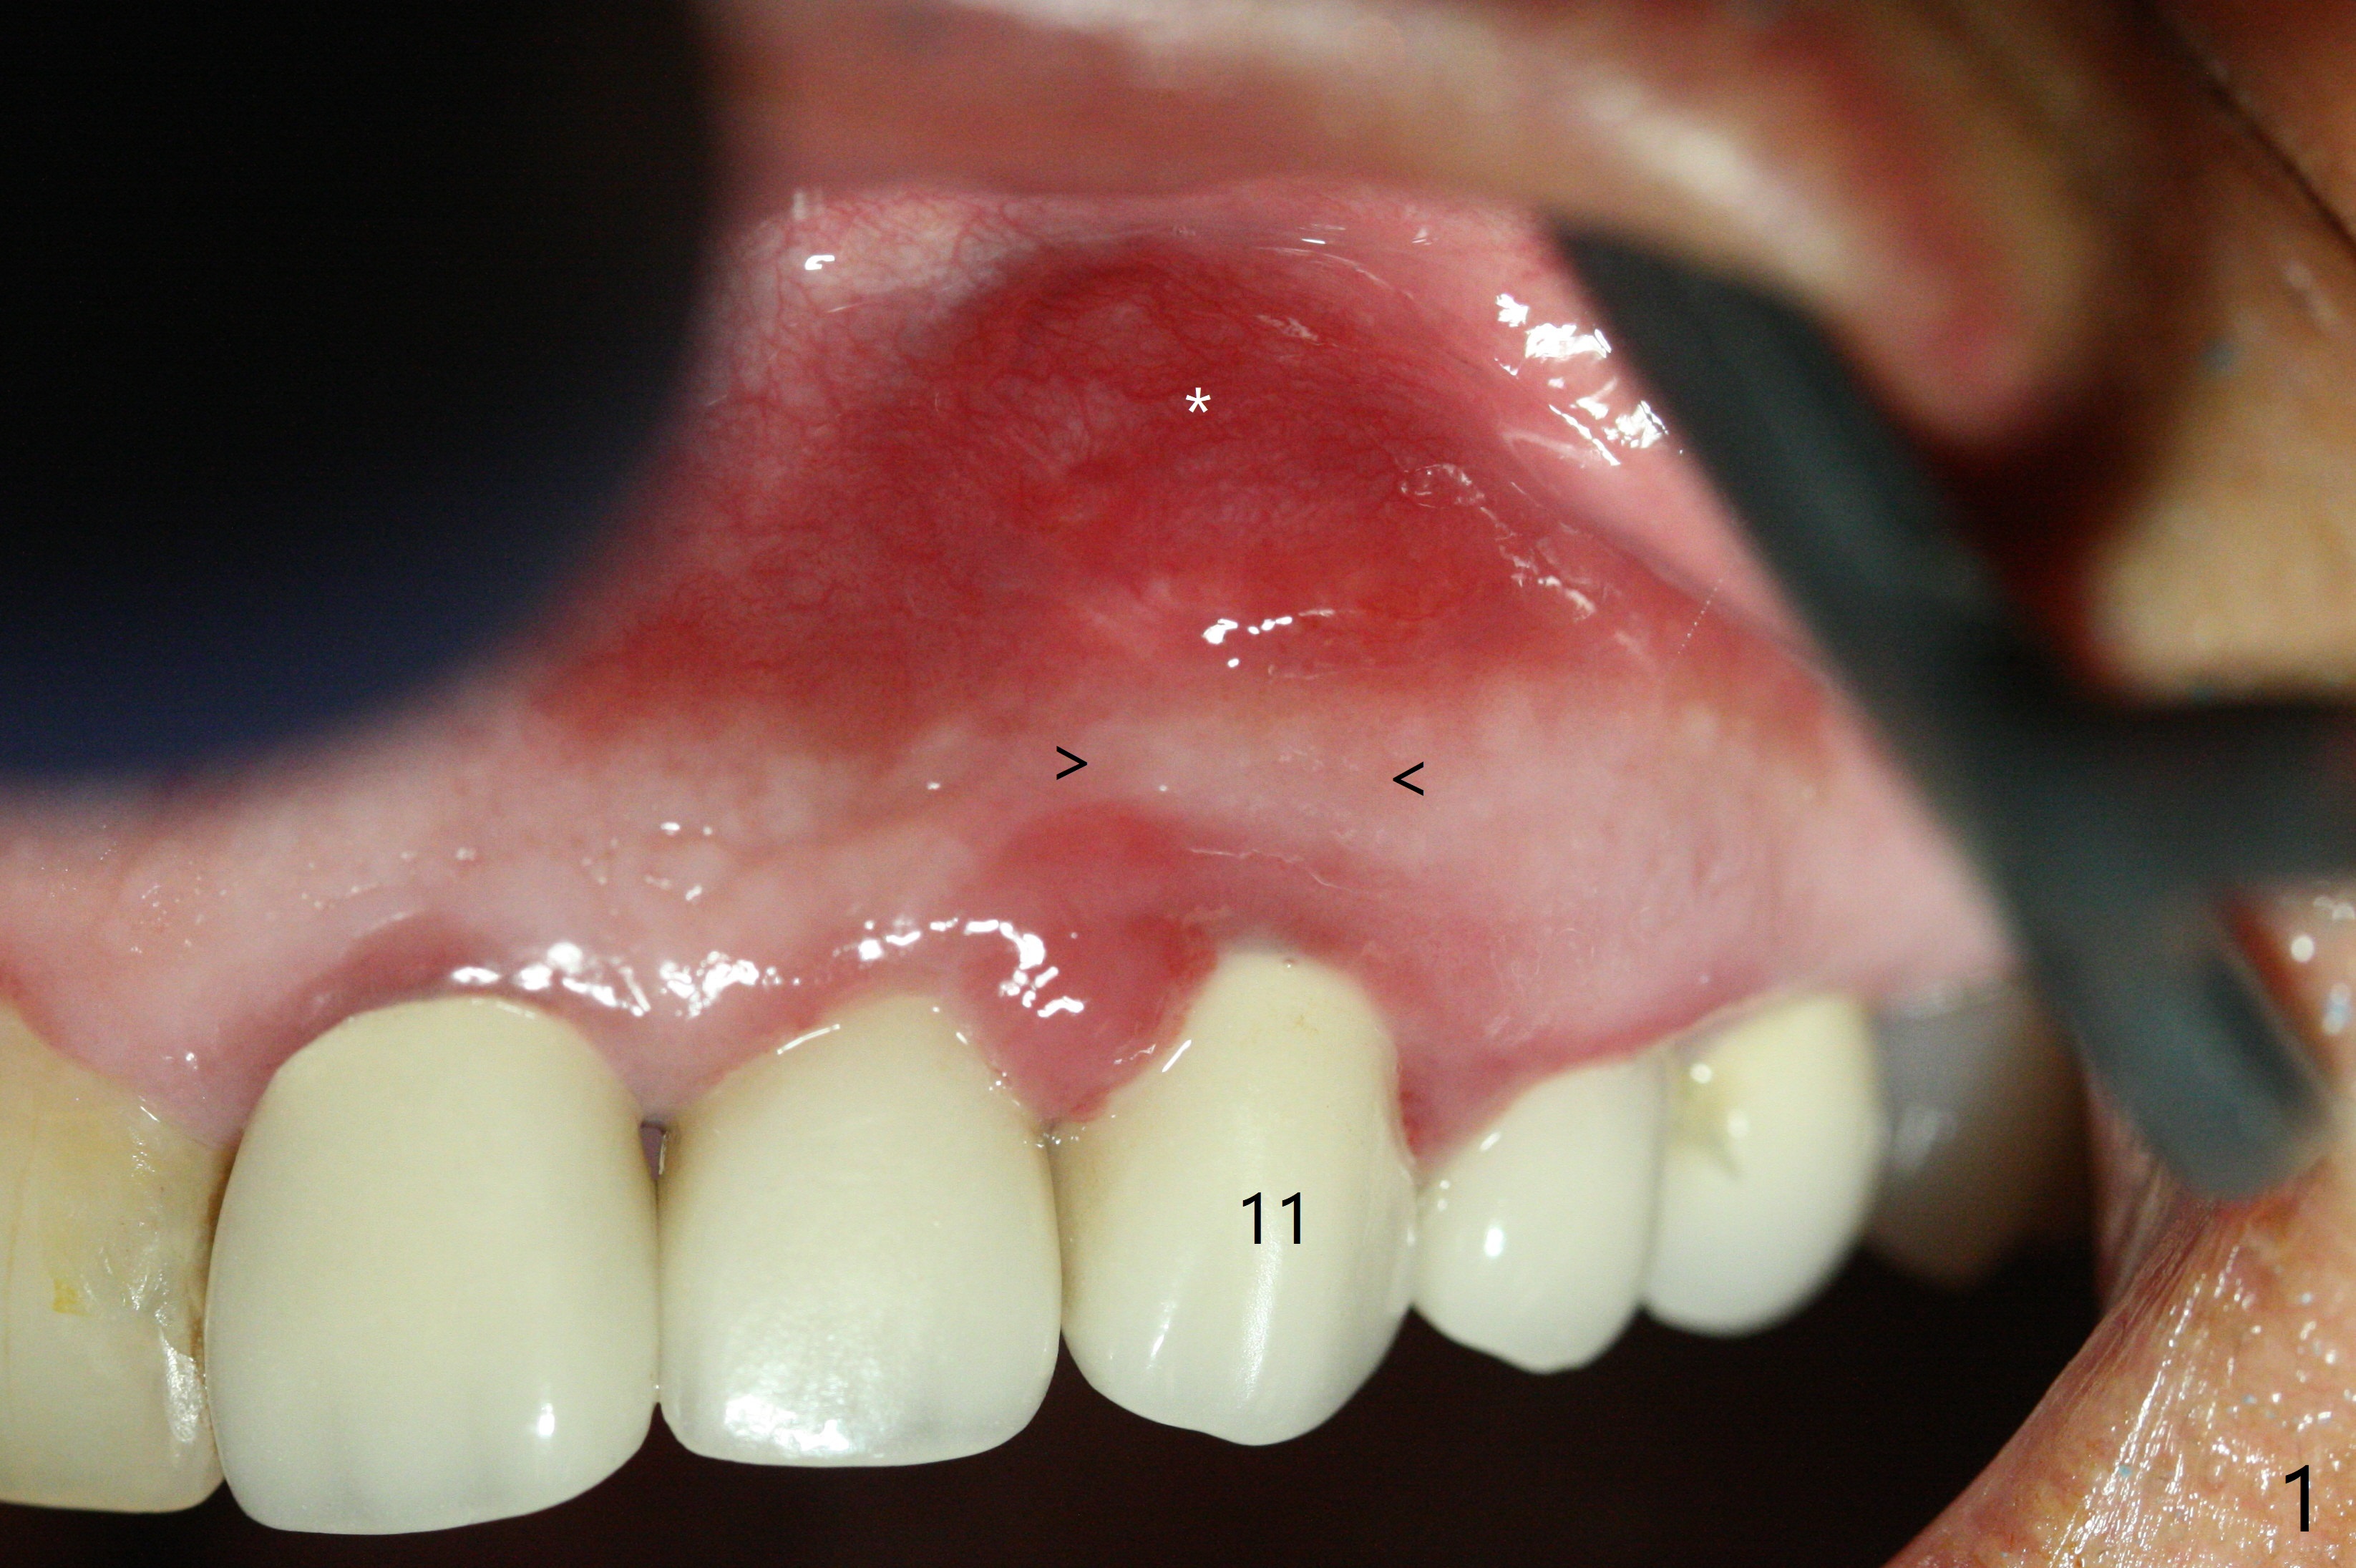

In spite of severe apical infection (Fig1,2 *), a thin narrow strip of the buccal plate (arrowheads, corresponding to the keratinized gingiva) is present when the tooth #11 is extracted. The thin bone keeps the bulging alveolus, i.e., reservoir for bone graft (Vanilla/Osteogen Fig.4 *) after placement of a 3.8x16 mm implant (Fig.3,4). A 4.5x1 mm temporary abutment, placed and trimmed for an immediate provisional, seems to be short in cuff. When an implant is placed deep to prevent periimplantitis, the cuff should be longer, i.e., 3 mm. X-ray should be taken for the depth confirmation after temporary abutment placement. Eight days postop, the mesial gingiva erythema has subsided (Fig.5 < (P: provisional)), while the apical swelling is no longer tender and most likely due to packed bone graft (*). Panoramic X-ray taken 2 weeks postop shows the clearance from the nasal cavity or the maxillary sinus (Fig.6). While the hard tissue around the implant seems to be healthy 5 months postop (Fig.7), the soft tissue is not (Fig.8). The temporary abutment is changed to a cemented one (4.5x5(2) mm) for impression (Fig.8). Since the neighboring crowns are PFM (Fig.6), the new crown will be made of the same material for shade match. Indeed PFM helps shade match in this case as well (Fig.9,10). Switching abutments (from temporary to cemented) makes it difficult to seat the crown. Post cementation X-ray leaves record for future contact loosening. The buccal gingiva remains erythematous associated with open margin (Fig.11 >) 1 year 4 months post cementation. There is no obvious bone loss 1 year 4 months post cementation (Fig.12). It appears that the crown and abutment need to be changed. Although the gingival margin remains erythematous, the gingival hemorrhage is basically lacking due to better oral hygiene during Shelter at Home (1 year 9 months post cementation, Fig.13). Change in abutment and crown will be conducted post coronavirus pandemic. In fact the abutment is incompletely seated (Fig.14 <). In addition, the tooth #12 is symptomatic with PARL associated with the buccal root (*). CBCT indicates possible buccal root fracture (Fig.15,16 ^) and loss of the buccal plate (Fig.16 <).